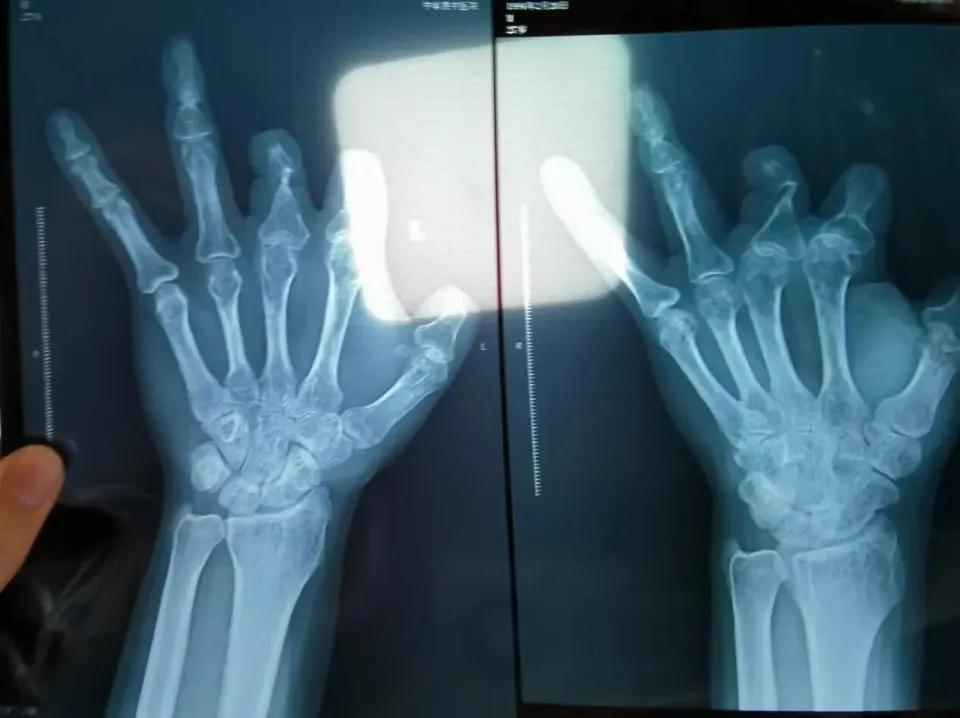

好在,终究是邪不压正。几个较真的病人,一张张空白的X光片,成了最硬的证据。那个王医生最后被判了12年,真是该!但判刑不是终点,我更希望的是,这套能让“投诉没用”的系统能真正改一改。医生的天职是“有时去治愈,常常去帮助,总是去安慰”,而不是反过来,把病人的痛苦和信任,变成自己计算器上跳动的数字。